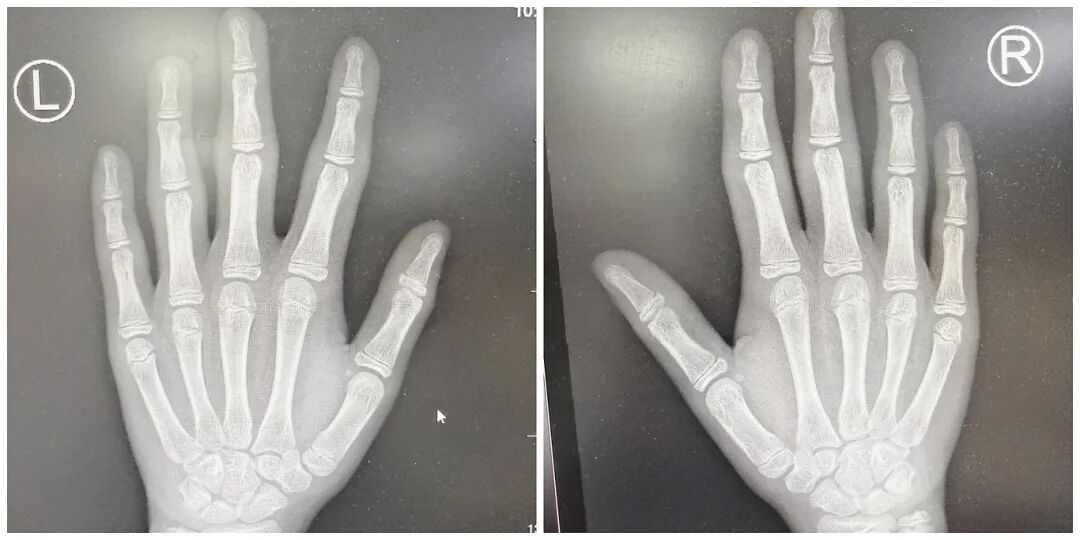

X光片显示,小烨双手指间关节仅有周围软组织肿胀,没有关节间隙狭窄、骨侵蚀、骨膜反应或骨质疏松等异常,这与类风湿关节炎等炎症性关节炎的典型表现有着本质区别;验血结果也同样印证了这一点,抗 O、类风湿因子、ANA、CCP 等炎症指标均为阴性,血沉和 CRP 也处于正常水平。

无系统性炎症指标升高、无自身抗体、无影像学骨关节破坏,且症状局限于手指。综上,小烨最终被明确诊断为厚皮指症。